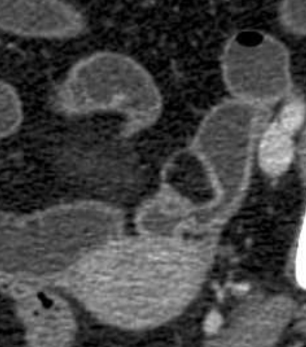

Lipome de

intestin grele : :Masse ovoide a bord lisse et

a hypodense de intestin . Image TDM en coupe coronal |